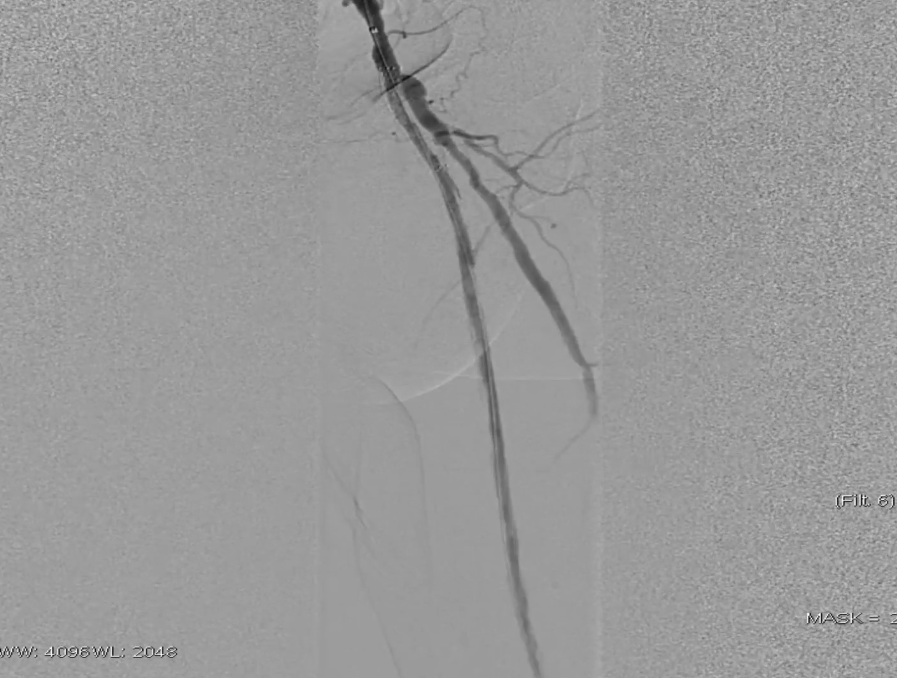

穿刺与造影定位

穿刺右侧股总动脉,置入8F翻山鞘,行左下肢动脉造影,可见左股浅动脉长段闭塞,远端流出道尚通畅。

既往支架已遮盖股浅动脉起始段